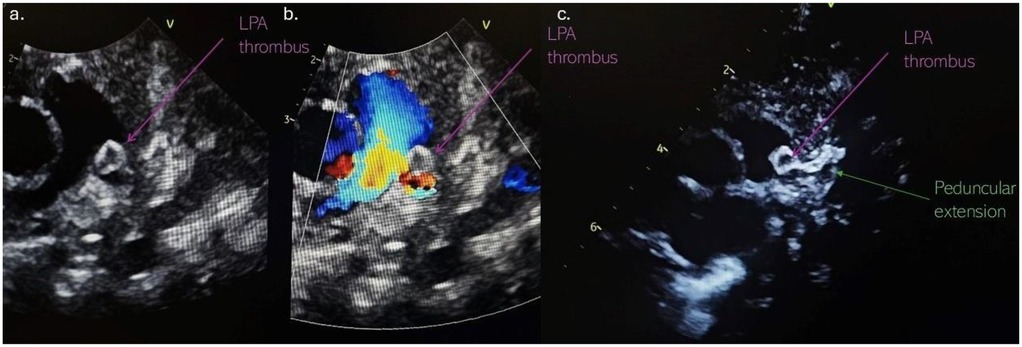

At the follow-up examination 2 weeks later, echocardiography revealed a pedunculated mass 5 mm × 5 mm suggestive of a thrombus, partially obstructing LPA with a pressure gradient of 30 mmHg. The mass was attached to a hyperechoic, tortuous peduncle, suspected to originate from a PDA, with a length of 11 mm (Figure 2). Due to these findings, the infant was admitted to the neonatal intensive care unit department. Upon admission, he remained clinically stable, with SpO2 of 100% and no signs of respiratory distress or cyanosis.

Figure 2. (a) Thrombus localised in the left pulmonary artery; (b) partially LPA obstruction with an accelerated blood flow in the LPA; (c) the thrombus attached to a hyperechoic, tortuous peduncle, suspected to originate from a DA. LPA, left pulmonary artery; DA, ductus arteriosus.